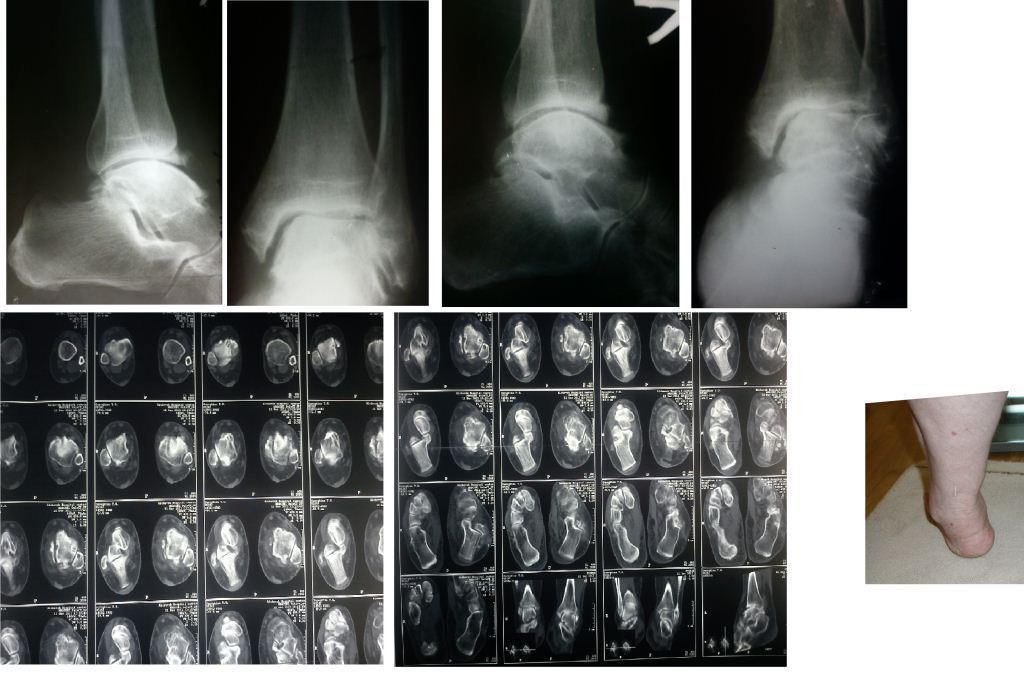

Уважаемые коллеги. Пациентка 1948 г.р., беспокоят боли в области левого голеностопа, прогрессирующая деформация(варусная) и неустойчивость сустава.Травму отрицает. Болеет более 5-ти лет. Согласна на операцию. Вопрос об артродезе г/ст сразу не вызывал сомнений. Но, если это артропатия, то насколько велик риск несращения? Помогите определиться с диагнозом и сответственно с тактикой. Невролог патологии не находит. Во вложенных файлах рентгенограммы за 2007 и 2012 гг.? фото и КТ свежая.

Вопрос, как я писал, в том что это такое- артропатия или артроз. Мне, например, не доводилось видеть нетравматический остеоартроз голеностопного сустава с прогрессирющей варусной деформацией и выраженной кистозной перестройкой. А несращение после резекции голеностопа у больного артропатией видел. В том случае коллеги дважды фиксировали блокирующим гвоздем и пациент ходил, пока держал металл и в настоящий момент планируется 3 синтез.

It looks like an end-stage probably either of neuropathic joint or Tibialis Posterior insufficiency.

У пациентки резко выраженная вальгусная деформация стопы. При попытке выполнения артродеза без коррекции оси конечности вероятность несостоятельности артродеза и сохранения болей крайне велика. Артроз имеет односторонний характер и связан, с большой степенью вероятности, с нарушением оси конечности. При восстановлении правильной оси такой сустав сможет послужить еще не один год. В плане дообследования обязательны снимки в переднезадней проекции под нагрузкой с захватом бугра пяточной кости, которые помогут лучше оценить осевые взаимоотношения голени и стопы. Исправить эти взаимоотношения можно, как путем медиализирующей остеотомии пяточной кости, так и путем остеотомии большеберцовой кости. Сохраняющая голеностопный сустав хирургия сейчас на подъеме, ей посвящаются симпозиумы, статьи. Она служит, как для сохранения сустава, так и для подготовки последующих успешных операций артродезирования или протезирования.

Во вложении - пример операции при гораздо более грубом посттравматическом артрозе, позволившей пациенту 61 г. через 1.5 г. после корригирующей остеотомии не думать о следующем вмешательстве. Хотя, есть работы, показывающие, что максимальный эффект после подобных остеотомий развивается к двум годам.